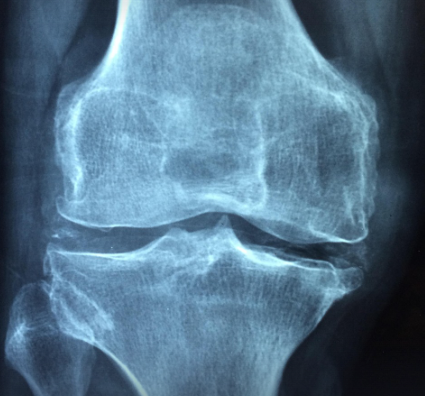

나이가 들수록 가장 먼저 느껴지는 변화 중 하나가 바로 ‘무릎 통증’입니다. 계단을 오르내릴 때, 쪼그려 앉을 때 무릎이 시큰거리고 삐걱대는 느낌이 든다면 연골의 손상이 시작된 것일 수 있습니다. 이런 증상을 완화하기 위해 많은 분들이 찾는 성분이 바로 콘드로이친(Chondroitin) 입니다. 그렇다면 이 성분이 정말 관절 통증에 효과가 있을까요? 과학적 근거를 바탕으로 콘드로이친의 효능과 한계를 정리해봤습니다.

콘드로이친은 연골을 구성하는 대표적인 다당류 성분으로, 관절을 보호하고 윤활 기능을 유지하는 데 중요한 역할을 합니다. 쉽게 말해 연골 속 ‘쿠션’ 역할을 하는 물질로, 충격을 흡수하고 관절이 부드럽게 움직이도록 돕습니다.

콘드로이친은 연골 내 수분을 유지해 마찰을 줄이고, 손상된 연골 조직의 재생을 돕습니다. 이는 노화나 과도한 운동으로 약해진 관절에 특히 도움이 됩니다.

연골이 닳으면 염증 반응이 생기고 통증이 발생하는데, 콘드로이친은 염증 매개 물질의 생성을 억제해 통증을 줄이는 데 기여합니다. 특히 퇴행성 관절염 환자에게 통증 감소 효과가 관찰된 바 있습니다.